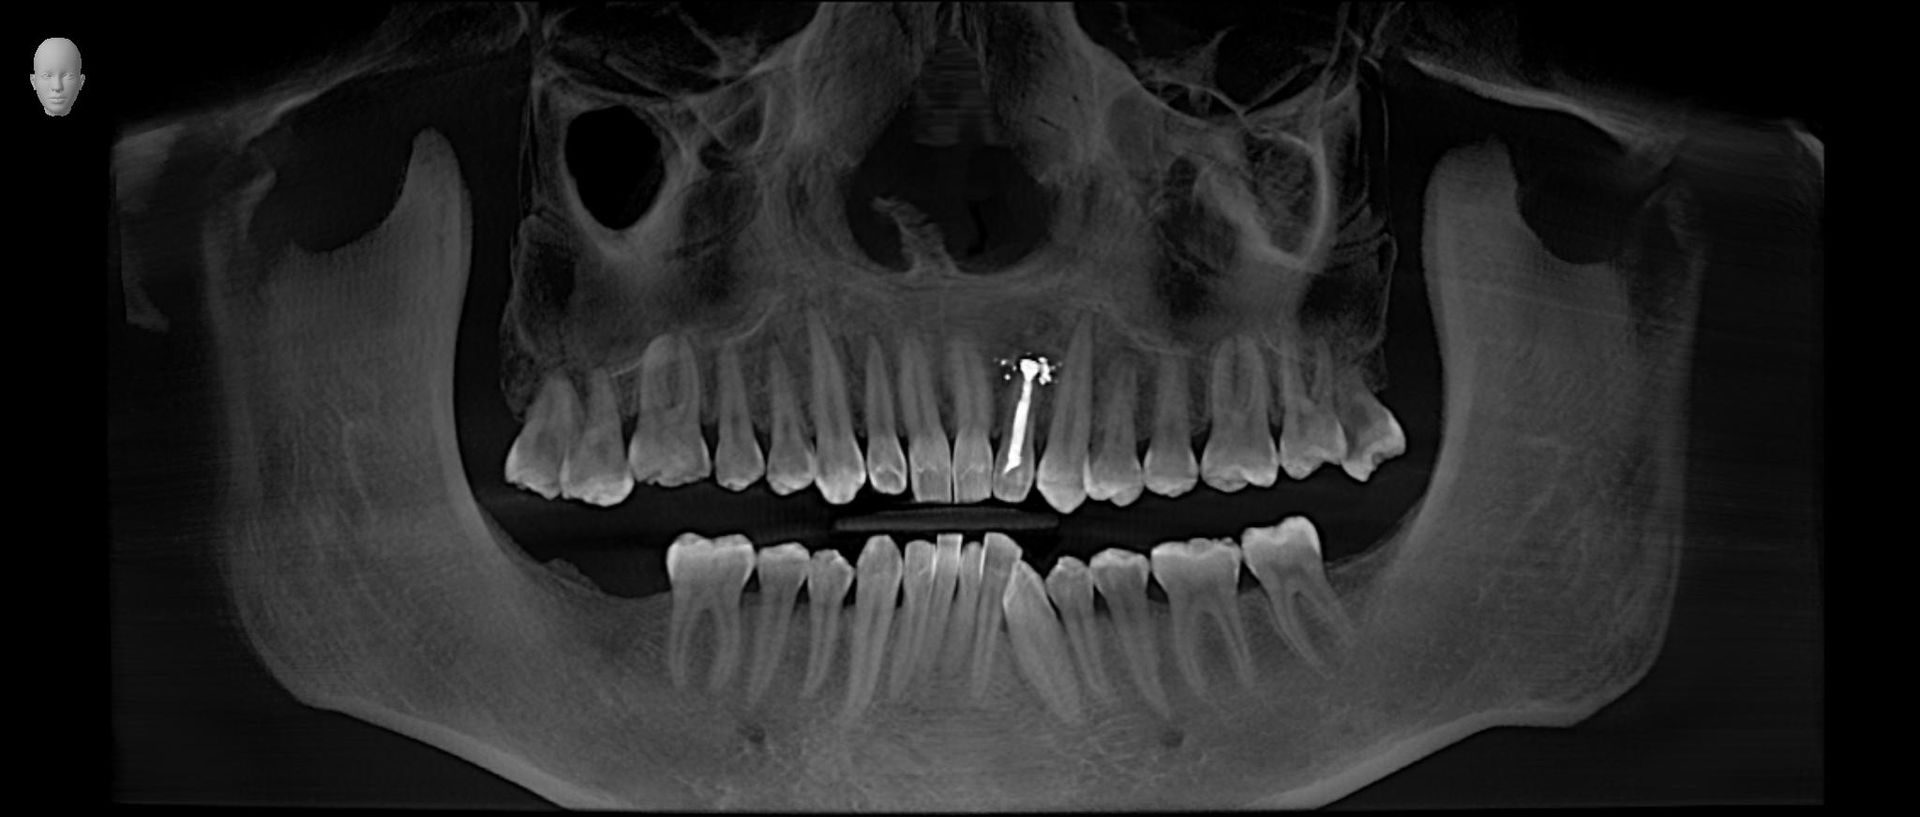

Esame diagnostico che permette di valutare, con precisione, la densità ossea mascellare e mandibolare, richiesto dai dentisti, in quanto indispensabile prima di un intervento di implantologia.

Trova indicazione anche in ortodonzia per lo studio dei denti inclusi, soprannumerari ed ectopici e in endodonzia.

La nostra struttura utilizza un’apparecchiatura radiologica di ultima generazione (Sirona Orthophos SL 3 D), che permette, in un’unica soluzione, di effettuare esami di arcate dentarie, cefalometrici e volumetrici 3 D).

Il nuovo sensore, a conversione diretta, garantisce precisione, con immagini più nitide, dettagliate e a bassissima emissione di raggi X (da 5 a 20 volte inferiore rispetto alla TC tradizionale); con bassissima dose per il paziente; quindi molto adatta ai pazienti più piccoli.

La funzione 3D, permette la visualizzazione completa delle strutture dentarie, ossee, in tre dimensioni, con ottima risoluzione di contrasto per lo studio dei tessuti molli.